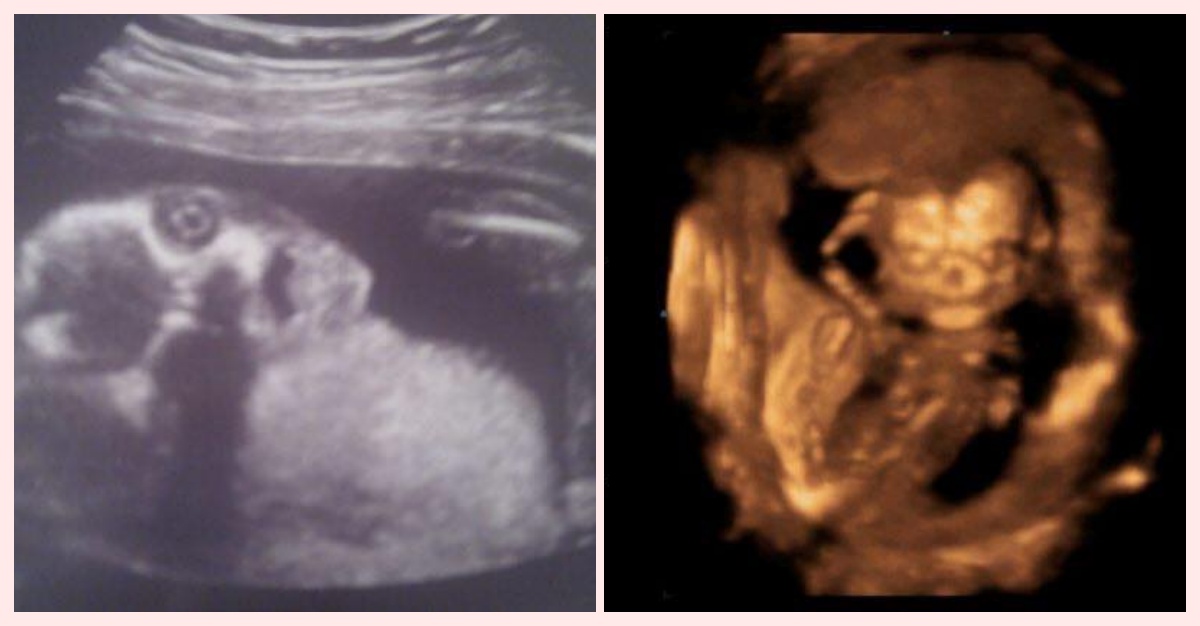

11 Ecografías Impactantes Que En Vez De Ternura Causan Escalofríos